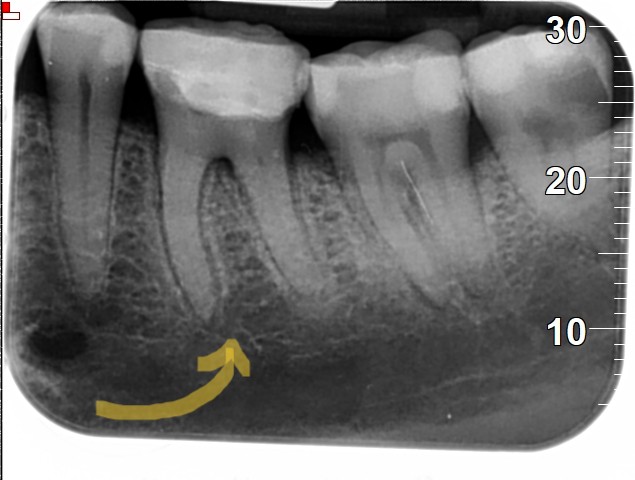

אותה מטופלת שן 26

אותה מטופלת שן 16

הסיפור של המטופלת לעיל מדגים באופן הטוב ביותר את החשיבות של גישה שמרנית יותר, המנסה להימנע מטיפול שורש. צילומי השיניים לעיל ניטלו לפני כשנתיים. בעת הגעתה למרפאתנו, הגיעה עם תלונה על כאבים בשן 26 (ראו צילום לעיל), לאחר שבוצע בשן זו טיפול שורש במרפאה קודמת בה היא הייתה. בשן בוצע טיפול שורש לפני כשנה טרם הגעתה למרפאתנו. הסיפור ארוך, אך בקצרה- בצילום סיטי (שבוצע בבית חולים מסיבות אחרות…) נראה כי טיפול השורש סבשן 26 היה נראה תקין לחלוטין (בד”כ יש 4 תעלות בשן זו בפה ומאוד נפוץ שמפוספת התעלה הרביעית אך אצל מטופלת זו היו רק 3 תעלות שורש שנאטמו יחסית טוב, לפחות רנטגנית). במהלך הבירור, המטופלת החלה לסבול מכאבים בשן 16, הוחלט לבצע VPT והיא נמצאת במעקב עד היום ללא כל תלונה על כאבים.